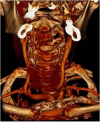

We report a case of a giant intra and extradural cervical schwannoma in a patient affected by a severe myelo-radiculopathy. Clinical features, diagnosis and the issues concerning the surgical management of this benign tumor are discussed. We also review similar cases previously reported in the literature. A 50-year old caucasian woman was complaining of a 1 year of neck pain and worsening motor impairment in all four limbs causing the inability to walk. Neuroradiological assessment revealed a suspected schwannoma involving the nerve roots from C3 to C5, compressing and deviating the spinal cord. The vertebral artery was also encased within the lesion, but still patent. A posterior cervical laminectomy with a microsurgical extradural resection of the lesion was performed. Moreover, an accurate dissection of the lesion from the vertebral artery and the resection of the intraspinal component was achieved. Vertebral fixation with screws on the lateral masses of C3, C5 and C6 and a hook on C1 was performed. The procedure was secured using electroneurophysiological monitoring. A progressive improvement of the motor functions was achieved. A cervical post-contrast MRI revealed optimal medullary decompression and a gross-total resection of the lesion. Schwannomas are benign, slowly growing lesions which may cause serious neurological deficit. Early diagnosis is necessary and it maybe aided by imaging studies such as MRI or CT. The accepted treatment for these tumors is surgical resection and, when indicated, vertebral fixation.